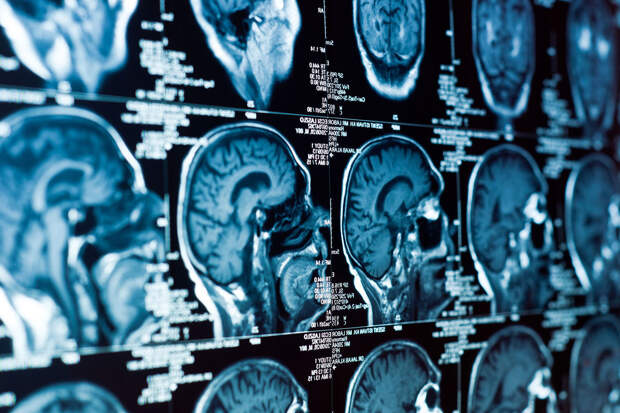

Ученые из Международного университета Флориды (FIU) установили, что повышение уровня белка 18 кДа в мозге может быть признаком ранней болезни Альцгеймера. Результаты исследования опубликованы в журнале Acta Neuropathologica (Acta Neuro).

Новая работа показала: повышенный уровень этого белка был зафиксирован у мышей с генетической предрасположенностью к заболеванию уже в шестинедельном возрасте — что эквивалентно примерно 18-20 годам у человека.Особенно высокие концентрации TSPO наблюдались в субикулуме — части мозга, регулирующей память. Аналогичные изменения также выявили в мозге девяти колумбийцев с редкой мутацией, вызывающей раннее развитие болезни Альцгеймера — в 30-40 лет.

"Нейровоспаление — это очень раннее событие при болезни Альцгеймера, которое влияет на ее начало", — отмечает нейробиолог Томас Гиларте из FIU. — "Если мы сможем использовать TSPO как инструмент ранней диагностики, это может отсрочить развитие симптомов на 5-6 лет и значительно улучшить качество жизни пациентов".